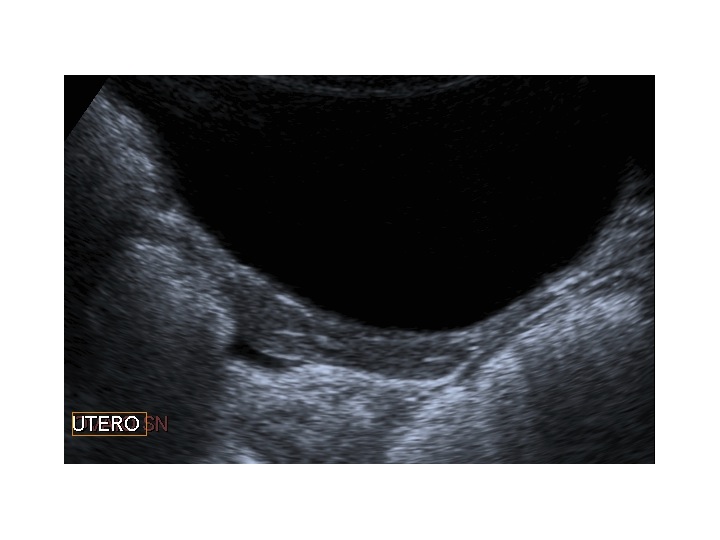

All’ecografia pelvica si osservano le ovaie a “banderella” (figura) e il cariotipo rivela l’assenza di un cromosoma X o la presenza di un mosaicismo, 45 X0/46XX nella forma più comune; nel 5% dei casi di ST può essere presente un frammento di cromosoma Y.

Dopo l'induzione di pubertà è ben visibile la rima endometriale (nella paziente 2 era appena accennata anche nelle immagini pre-terapia), soprattutto nelle sezioni longitudinali, con l'assenza di follicoli a livello ovarico